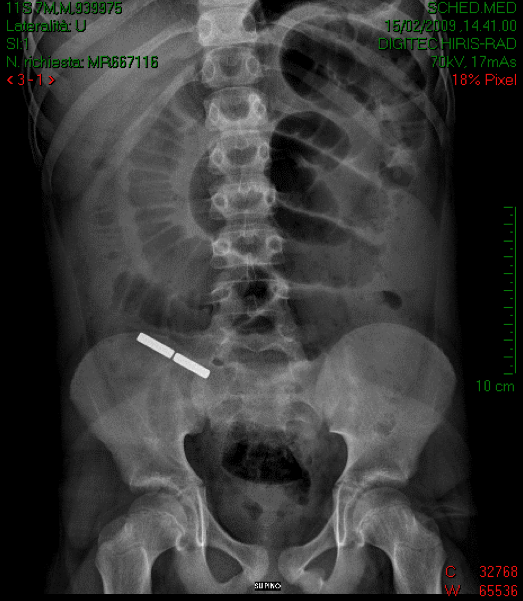

Figura 1 All'apertura del peritoneo si assiste alla fuoriuscita di abbondante materiale corpuscolato. Le anse ileali sono ectasiche ed edematose, con presenza di due piccole aree di perforazione, in corrispondenza dei due corpi estranei. Attraverso il lume appendicolare viene poi estratto un corpo estraneo cilindrico, magnetico, che attira lo strumento chirurgico. Viene inoltre resecata una tenace briglia occludente, verosimilmente congenita, a valle delle anse ectasiche. L'Rx addome di controllo mostra poi la presenza di un altro corpo estraneo metallico, analogo a quello rimosso in sala operatoria, proiettantesi sul sacro, che viene poi espulso spontaneamente in 10� giornata post-operatoria (Figura 2).

Figura 2 A M., al ritorno dalla terapia intensiva, dove � rimasto ricoverato nel postoperatorio per una complicanza, vengono mostrati i due corpi estranei, che risultano essere due pezzetti di GeoMag, un gioco di costruzioni fatto di piccole stanghette fortemente magnetizzate e sfere metalliche e�finalmente confessa di averli mangiati circa 1 settimana prima, ma di non averlo riferito n� ai genitori n� ai medici per paura di essere sgridato! La morale �.mai fidarsi dell'anamnesi, anche se fatta da pi� medici e anche se ripetuta! |